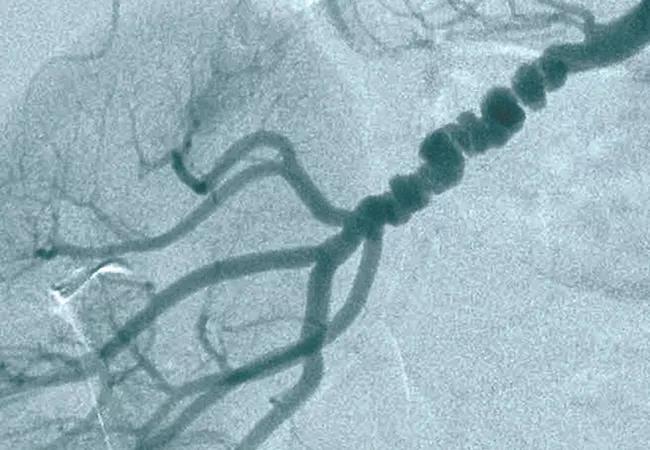

Fibromuscular Dysplasia: Diagnosis at Later Age Suggests Milder Course

When multifocal fibromuscular dysplasia (FMD) is diagnosed at an older age, its course appears to be more benign and less symptomatic than when recognized in middle age, concludes a new analysis of the U.S. Registry for Fibromuscular Dysplasia published in JAMA Cardiology.

Most cases of FMD — an uncommon, nonatherosclerotic arterial disease that predominantly affects women — are diagnosed in middle age. Although presentation of FMD in older adults was previously recognized, the new study is the first to characterize the condition among patients 65 or older at the time of diagnosis, the authors note.